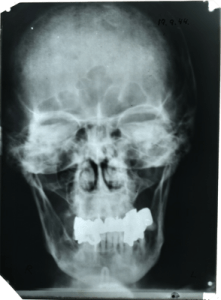

That part, the surgeon, I feel good about. In 2004, I went to Stanford for a history teachers’ seminar on America in the Depression, during the New Deal and in World War II. At the Hoover Institute, I got to hold this X-ray of Hitler’s skull, taken after the July 1944 bomb plot.